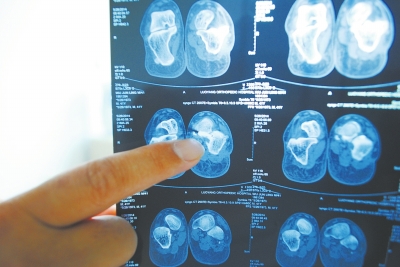

X光片顯示,確實有一根殘留的螺絲釘。

今年4月,正在浙江的吳俊領(lǐng)忽然感覺手術(shù)傷口處隱隱作痛,并有膿水流出。他到醫(yī)院拍片檢查后,被告知左腳跟傷口內(nèi)殘留有一根螺絲釘。

于是,吳俊領(lǐng)拿著X光片到太康縣民族骨科醫(yī)院討要說法?!澳悴皇钦f傷口內(nèi)的固定鋼板物被取凈了嗎?這X光片上咋還殘留一個螺絲釘啊?”一見到當(dāng)時給自己做手術(shù)的醫(yī)生,吳俊領(lǐng)就問道。醫(yī)生當(dāng)即準(zhǔn)備帶領(lǐng)吳俊領(lǐng)到手術(shù)室打開傷口查看情況,但吳俊領(lǐng)已對這家醫(yī)院失去信任,最終到洛陽市一家他信任的醫(yī)院做了殘留螺絲釘取出手術(shù),住院18天后康復(fù)出院。出院后,吳俊領(lǐng)要求太康縣民族骨科醫(yī)院院賠償其經(jīng)濟(jì)損失,但遭到拒絕。